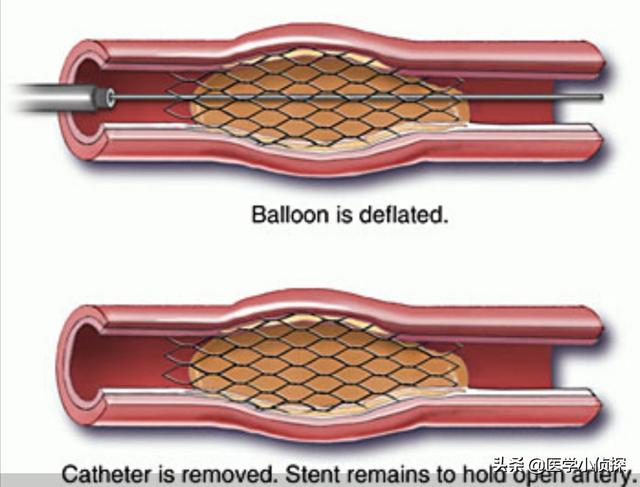

ステップ1、パンク。末梢動脈を見つけ、この動脈から穿刺を行うが、最も一般的な選択は、手の付け根か太ももの末梢動脈を選択することである。

ステップ2、チューブの挿入。その末梢血管開口部からシースを挿入し、適切なサイズのシースを選択してガイドワイヤーを進め、冠動脈開口部付近の心臓までゆっくりと送り込む。

ステップ3:軌道を確立する。最初のガイドワイヤーは冠動脈より太いので、この時は細いガイドワイヤーを選んで冠動脈病変の遠位部を通過させ、まずバルーンで拡張しなければならない。

ステップ4:ステントを留置する。バルーンの拡張が完了したら、このガイドワイヤーに従ってステントを留置する。

これが心臓ステント手術の大まかな流れだ。 経験を積んだ。熟練した医師は、この手術を30分以上かけて行う!そのため、心臓ステント手術を専門とする医師にとっては、そうである。大きな作戦ではない。。